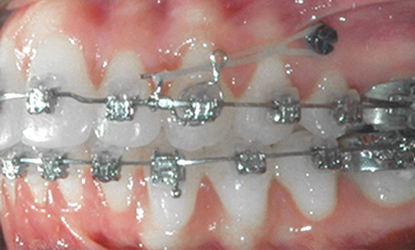

Jednostronne użycie Dystalizera Carriere

>   Jednostronne użycie Dystalizera Carriere w przypadku zaburzonych triad (wzajemne kontakty zębów górnych i dolnych) zabezpieczenie wyników leczenia miniimplantem ortodontycznym.